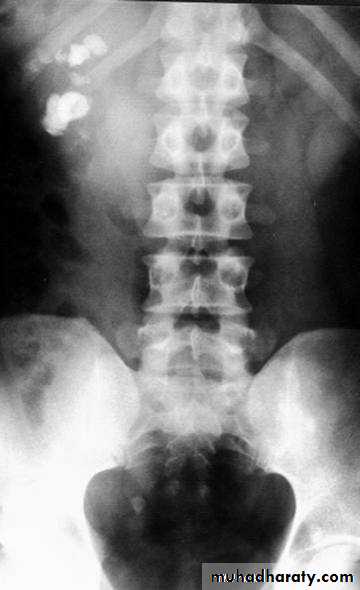

1-Renal function test:More than 70% of renal function must be lost before renal failure becomes evident2-Blood urea & serum criatinin 3-radiological:- KUB (kidney,ureter,bladder):-A-BonesSB-Soft tissueC-StonesA plain radiograph of the abdomen and pelvis includes the area above both adrenal glands and extends to 2 cm below the symphysis pubis

KUB: site, skin, sex, stones, psoas shadow, skeleton, and soft tissue shadow